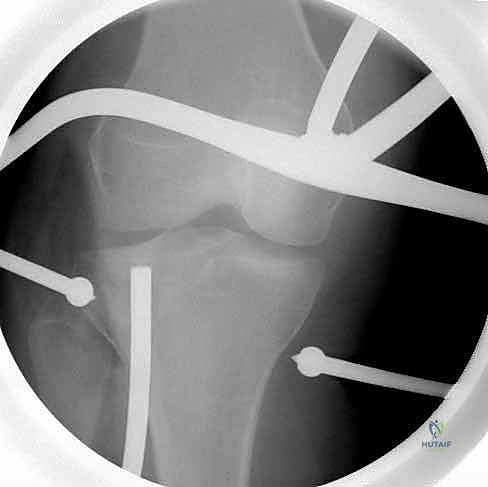

التدخل الجراحي (ORIF): خطوة بخطوة مع الأستاذ الدكتور محمد هطيف

التثبيت الداخلي المفتوح (Open Reduction and Internal Fixation - ORIF) هو الإجراء الجراحي القياسي لكسور الهضبة الظنبوبية الجانبية المزاحة. بفضل خبرته الواسعة وتدريبه المتقدم، يُجري الدكتور هطيف هذه العمليات بدقة متناهية.

5. رد الكسر ورفع الانخساف (Reduction & Elevation)

هذه هي الخطوة الأكثر دقة. يقوم الدكتور هطيف بفتح نافذة صغيرة في عظم الساق أسفل الكسر، ويستخدم أدوات خاصة لدفع العظم المفصلي المنهار إلى الأعلى حتى يعود إلى مستواه الطبيعي تماماً، ليطابق الهضبة الإنسية.